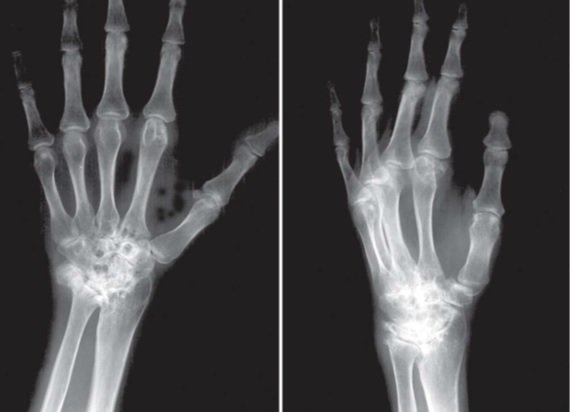

وی با بیان اینکه امکان تصویربرداری و مونیتورینگ برای جراحان پیشبینی شده است، اضافه کرد: این ابزار به دستگاه تصویربرداری اتاق عمل با عنوان CR متصل است و جراح همزمان با این کشش میتواند نحوه جا اندازی شکستگیها را مونیتور کند.

این محقق یادآور شد: این دستگاه در حالی امکان عکسبرداری حین عمل و پینگذاری تحت "فلوروسکوپی" را فراهم میکند که تاکنون چنین امکاناتی در اعمال جراحی ارتوپدی اندام فوقانی وجود نداشته است.

مجری طرح، امکان عکسبرداری همزمان با عمل جراحی از موضع عمل در شکستگیهای مچ دست و ساعد، امکان پینگذاری حین عمل تحت فلوروسکوپی برای شکستگیهای مچ دست و ساعد، قابل تنظیم بودن برای تمام سنین، کوتاه شدن زمان عمل جراحی، تسلط بیشتر جراح بر موضع عمل جراحی بهویژه در خصوص پین گذاری و امکان تنظیم اعمال کشش و اعمال نیرو بر موضع شکستگی در جهت جا اندازی و فیکساسیون شکستگی را از مزایای این دستگاه نام برد.